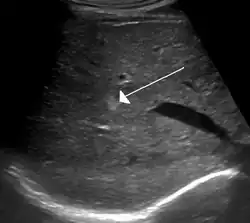

Hemangioma

Hemangiomas (do grego haema- (αίμα), "sangue"; angeio (αγγείο), "vaso"; -oma (-ωμα) "tumor") são angiomas, tumores vasculares benignos causados por um crescimento anormal de vasos sanguíneos que geralmente não causam danos, apenas são desagradáveis esteticamente. São mais comuns na pele, especialmente na cabeça e pescoço, mas podem aparecer em vários órgãos, como o fígado, o baço, o pâncreas, na boca ou em bolsas sinoviais.